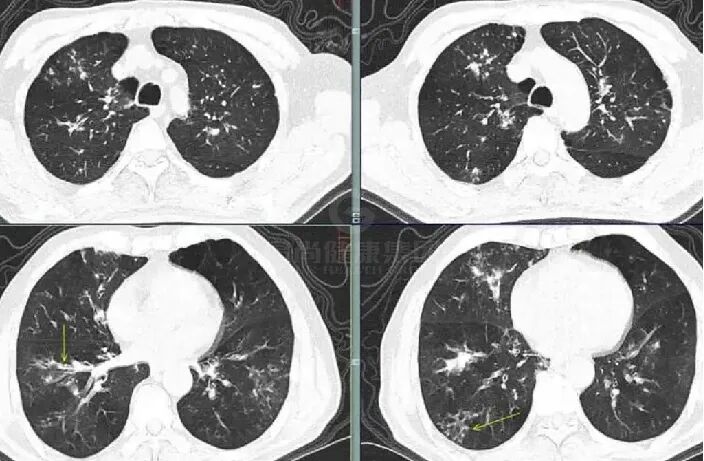

小叶中心性结节、树芽征 (多发),片状实变区,沿支气管周围分布。

支气管壁增厚,树芽征

肺真菌感染(如侵袭性曲霉病、隐球菌病等)早期诊断困难,真菌侵袭早期,肺泡壁水肿或出血可表现为 GGO,传统认为空洞和空气新月征是肺真菌感染的典型标志,但研究发现,这些征象特异性虽高,却常在中性粒细胞恢复期或感染后 2-3 周才出现,相比之下,磨玻璃影(GGO)、微结节、树芽征(支气管簇集征)、(反)晕征出现更早,却因非特异性被忽视。